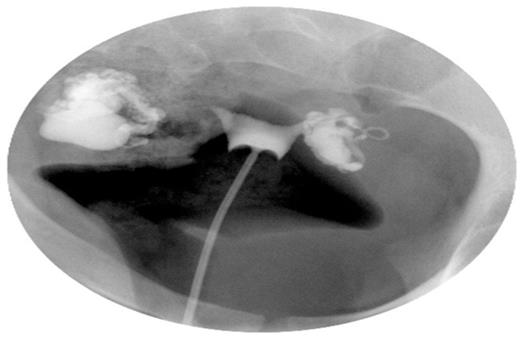

Hysteroscopic appearance of endometrial cavity immediately pre-salpingectomy (A) and six months after interruption of communication with hydrosalpinges (B). For each series, images from left to right depict right cornual, fundal and left cornual regions, respectively.

Six months later, the patient underwent hysteroscopic endometrial cavity evaluation in preparation for IVF. At hysteroscopy, a normal endometrium was visualized (Figure 2B). Specifically, the previously seen hyperemia and stromal oedema had resolved. The patient subsequently underwent IVF with transfer of a single blastocyst culminating in the delivery of a healthy infant at term.

As depicted in Figure 2, the endometrial surface appears erythematous with friable and tortuous vascularity in the setting of a hydrosalpinx, and normal appearing after surgical interruption of hydrosalpingeal drainage. Subsequent IVF treatment and transfer of a single blastocyst resulted in an intrauterine pregnancy, with subsequent term delivery, indicative of functional embryo receptivity on a molecular level, although no molecular evidence is available for confirmation.